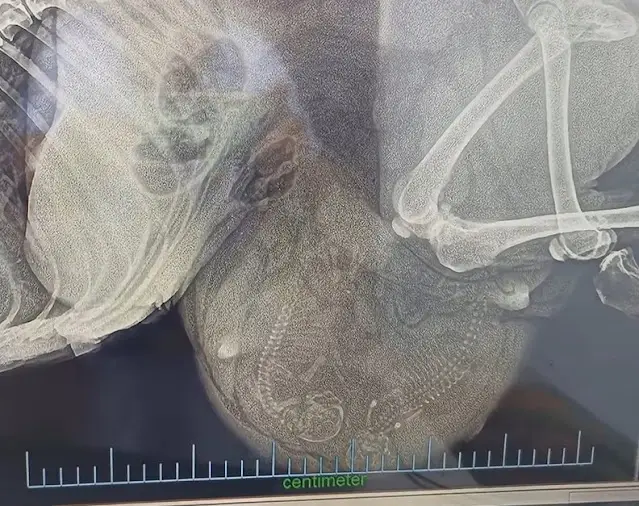

After a tense ultrasound, the vet shared news that left everyone speechless.

What they had thought was a tumor was something else entirely — two tiny heartbeats.

This dog, starved and broken, was pregnant. She had been fighting not just for her own survival, but for her unborn babies. Her collapse on the street wasn’t defeat — it was a final act of love.